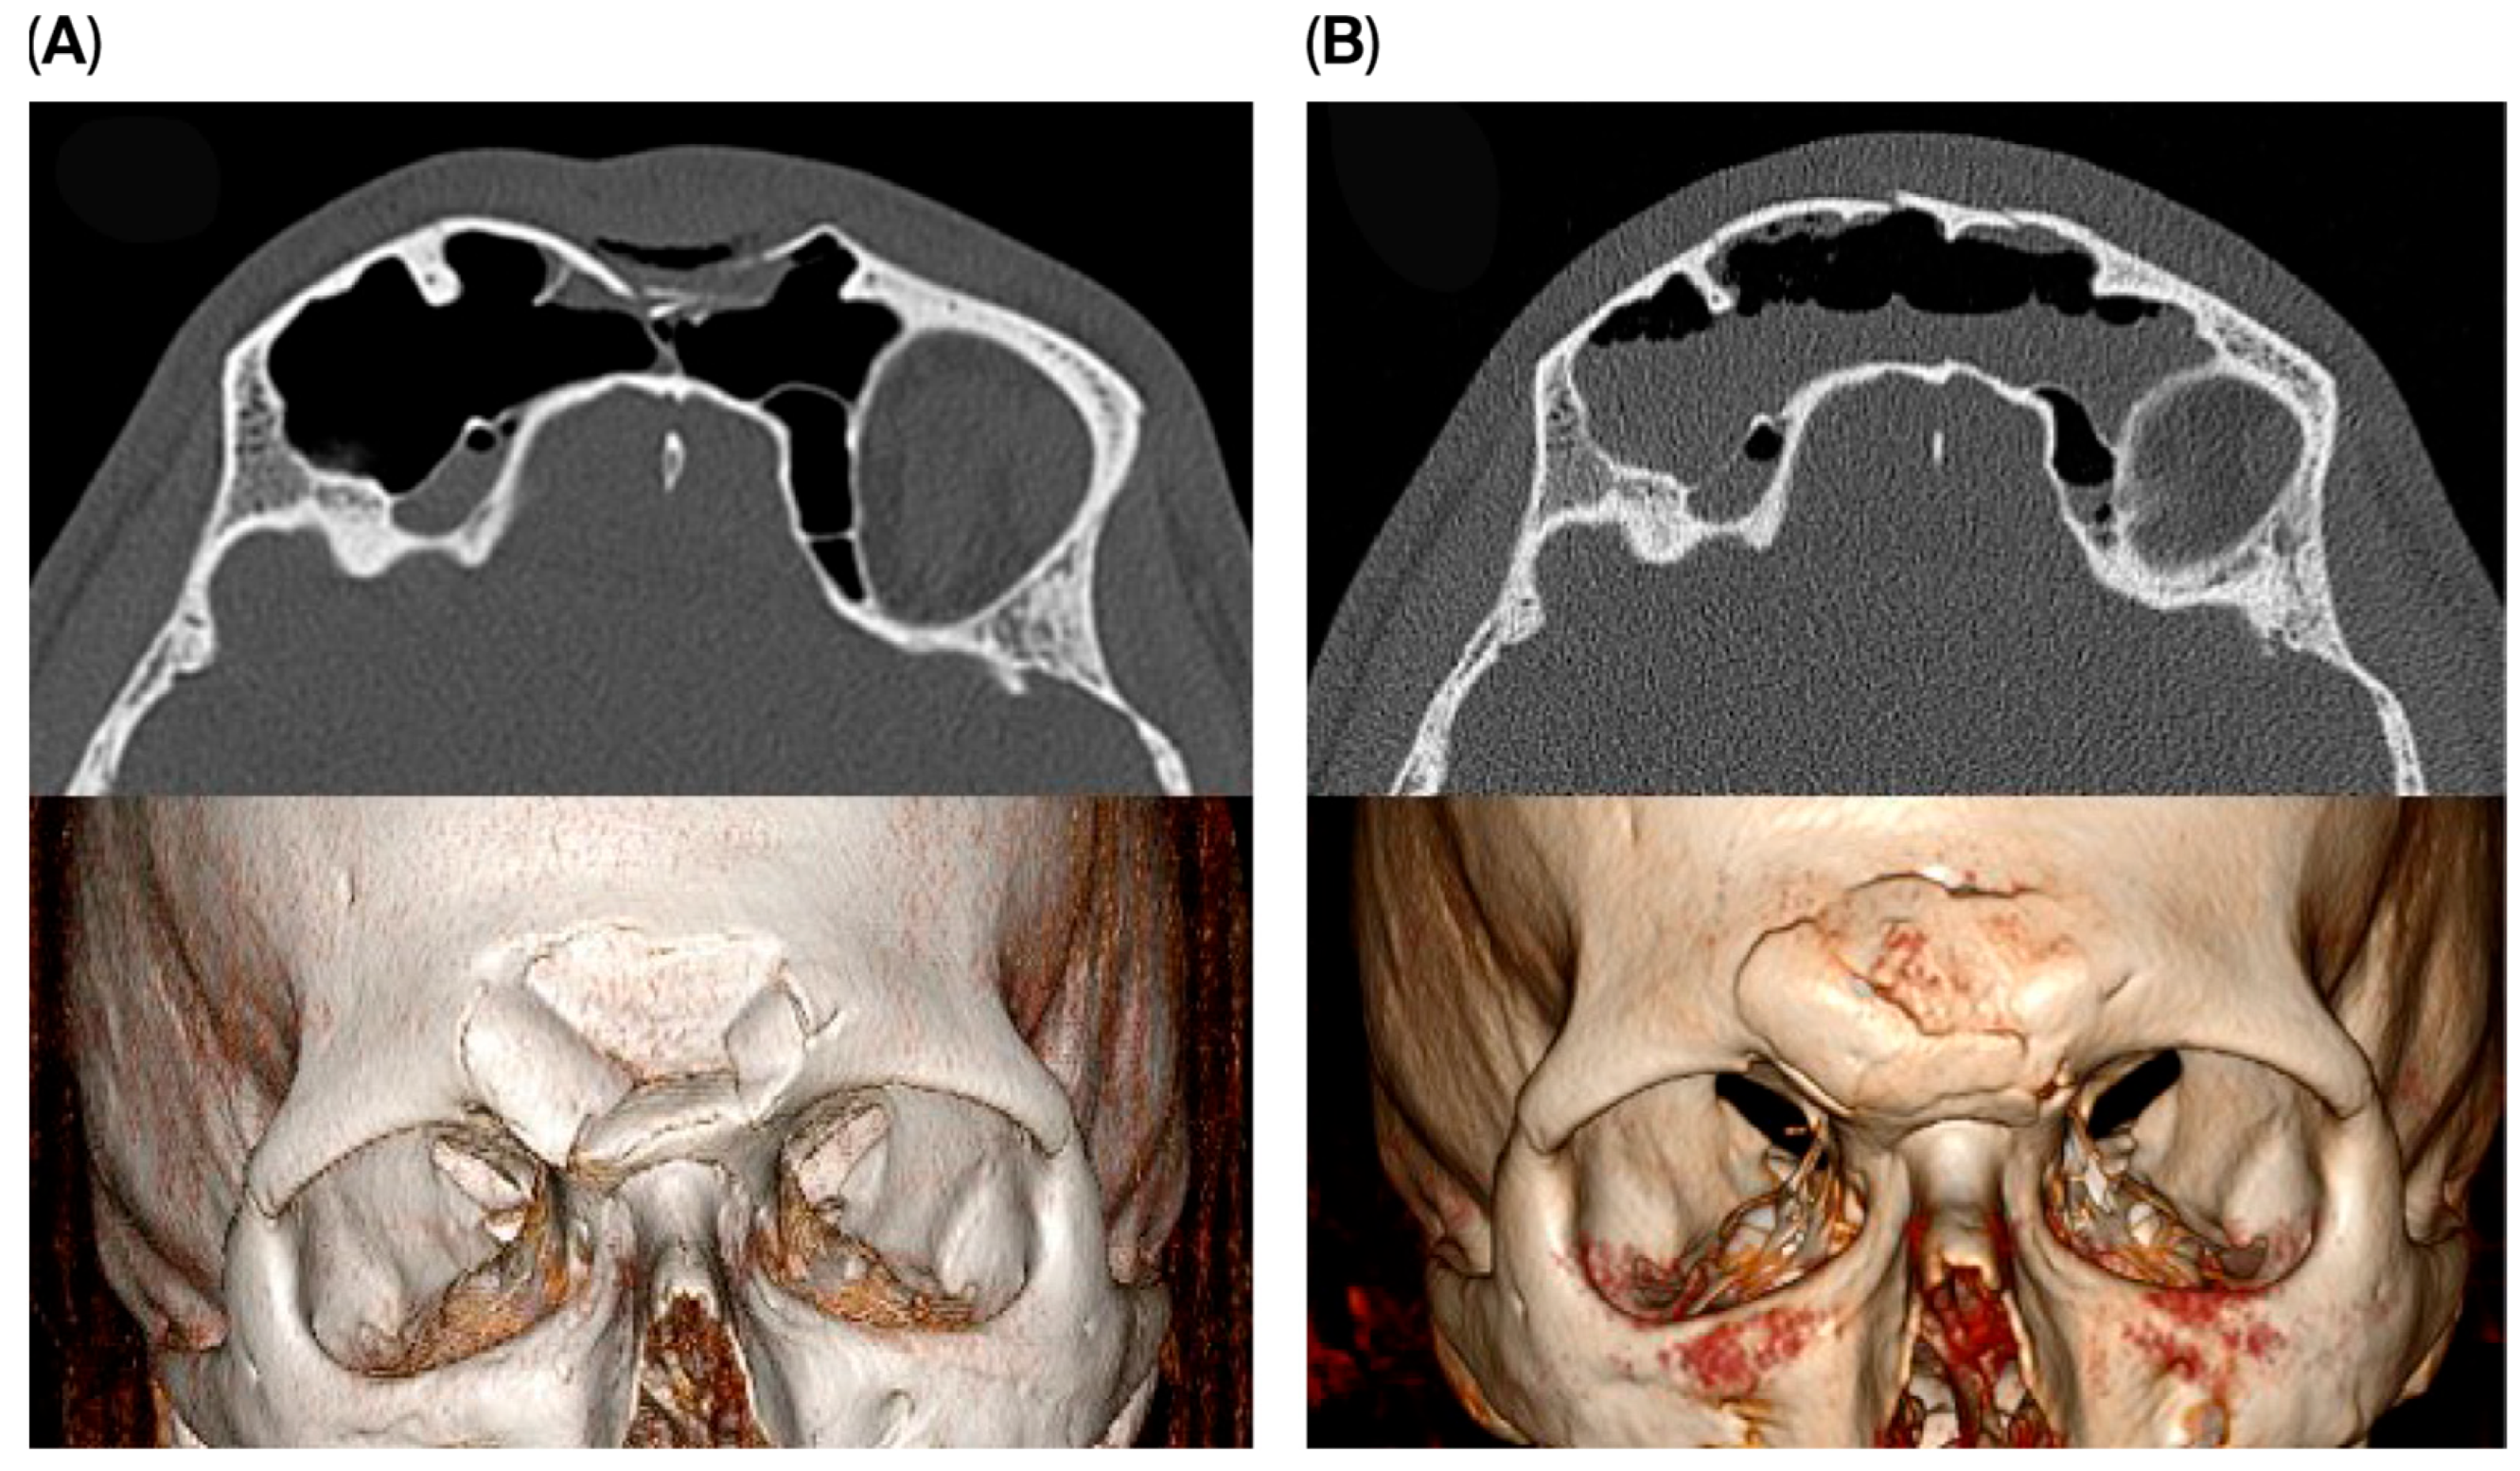

Osteosynthesis material was used in two cases within the endoscopic transorbital group to reconstruct the supraorbital rim and for stabilization of the fracture fragments. A small 1.5 plate was used to stabilize the fragments with fixation on the supra-orbital rim (Figure 4). The remaining four patients did not require osteosynthesis material. No impact on outcome was seen if osteosynthesis was used or not.

Figure 4. Pre- (A) and postoperative (B) images of a patient receiving the endoscopic transorbital approach with the use of osteosynthesis material for stabilization.